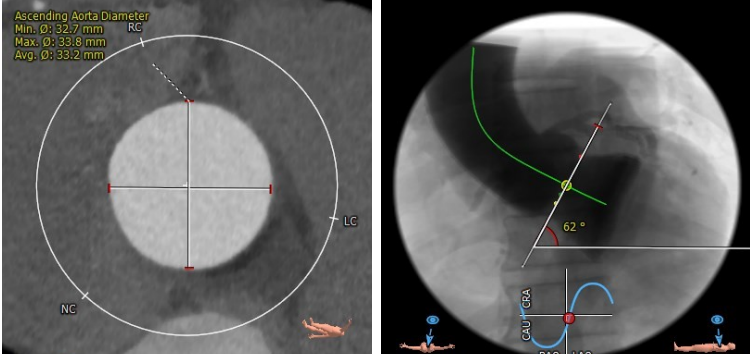

CTA主动脉根部解剖:

患者为三叶瓣,轻度钙化,右冠开口高度较高,升主动脉最宽处约33.2mm,横位心,心脏角度约62°,左室偏小。

Annulus Dimensions ——24.5mm

LVOT——25.5mm

Sinus——32.6*34*28.9mm

Stj——30.5mm

升主最宽处:33.2mm

心脏角度:62°

该病例为三叶瓣,瓣环直径24.5mm,左冠开口高度12.2mm,右冠开口高度17.4mm,升主最宽处达33.2mm,经核心实验室评估后 术中冠脉无堵塞风险,入路内径尚可,计划使用右侧股动脉为主入路,左侧股动脉为副入路。23mm球囊预扩张,使用Venus-A 29瓣膜。